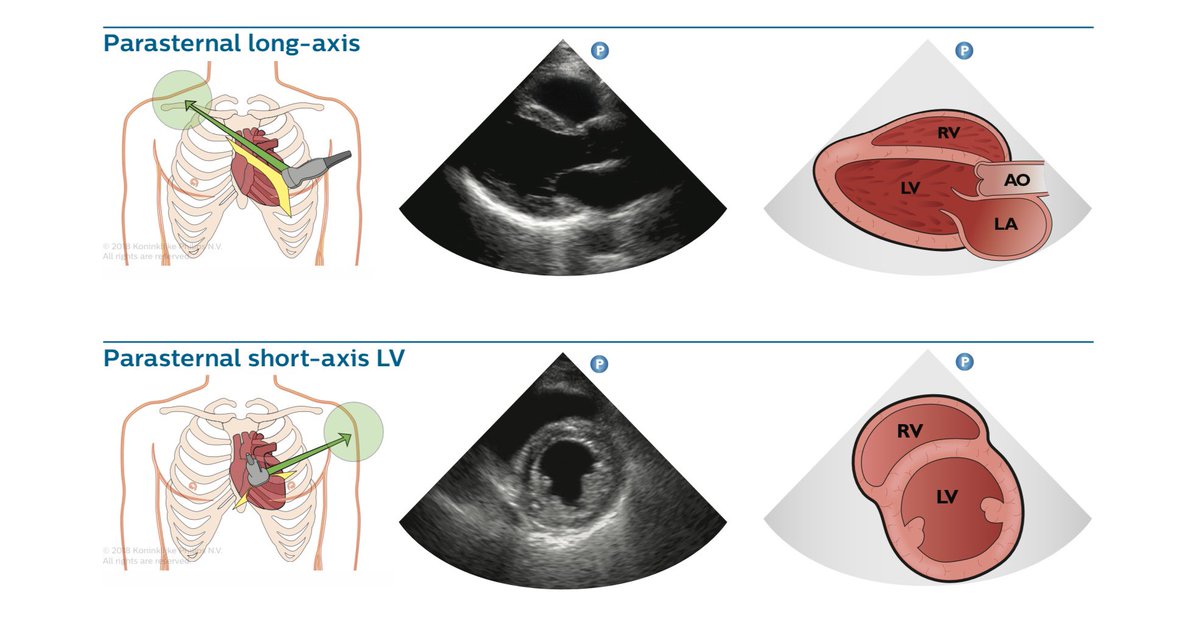

Cardiac POCUS using the short-axis left parasternal view showing ...

NephroPOCUS on Twitter: "Cardiac #POCUS views illustrations Courtesy of ...